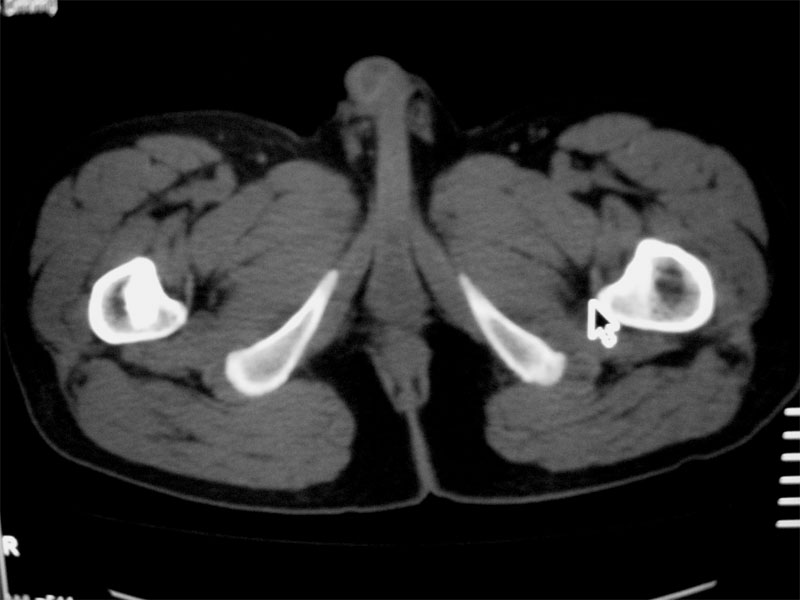

标题: CT16604:男32岁,左髋关节处疼痛月余 [打印本页]

标题: CT16604:男32岁,左髋关节处疼痛月余

左股骨头缺血性坏死

双侧股骨头坏死

考虑左股骨头缺血性坏死;建议必要时行mri检查。

考虑左股骨头缺血性坏死;建议必要时行mri检查。右侧拍平片

双侧股骨头坏死!!

左侧股骨头坏死,左侧髋关节少量积液

考虑左侧股骨头坏死。

考虑左股骨头缺血性坏死;右股骨上段良性骨肿瘤,考虑成软骨细胞瘤可能。建议上传骨窗。